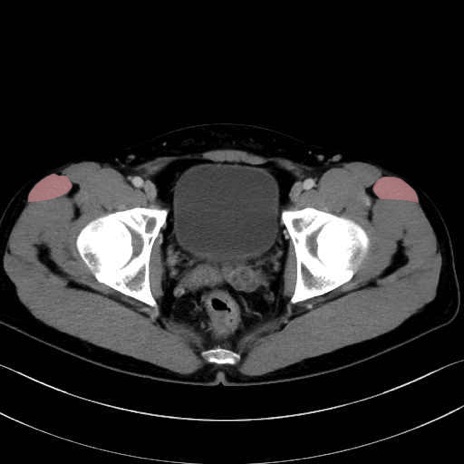

大腿筋膜張筋 (Tensor fasciae latae)